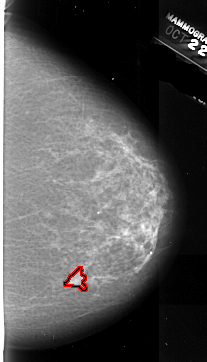

A_1008_1.RIGHT_MLO

RIGHT_MLO LINES 6526 PIXELS_PER_LINE 3826 BITS_PER_PIXEL 16 RESOLUTION 42 OVERLAY

FILE: A_1008_1.RIGHT_MLO.OVERLAY

TOTAL_ABNORMALITIES 1

ABNORMALITY 1

LESION_TYPE MASS SHAPE IRREGULAR MARGINS ILL_DEFINED

ASSESSMENT 4

SUBTLETY 4

PATHOLOGY MALIGNANT

TOTAL_OUTLINES 1

BOUNDARY